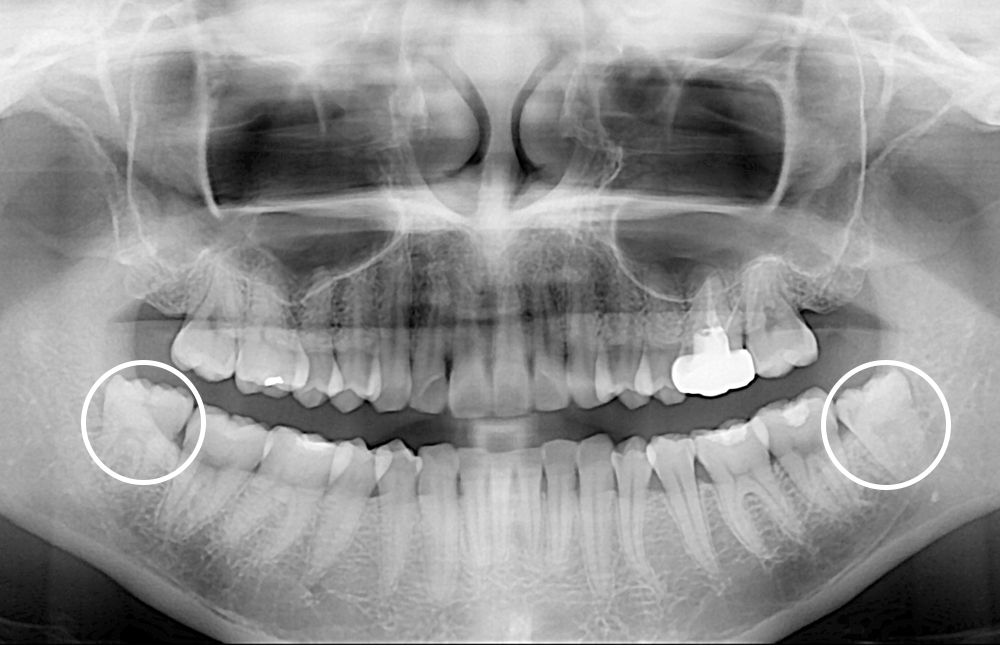

[사랑니] 매복 사랑니 발치

치료전 : 2016-01-12

세종치과는 구강악안면외과학 박사이신 원장님이 발치하는 치과입니다.